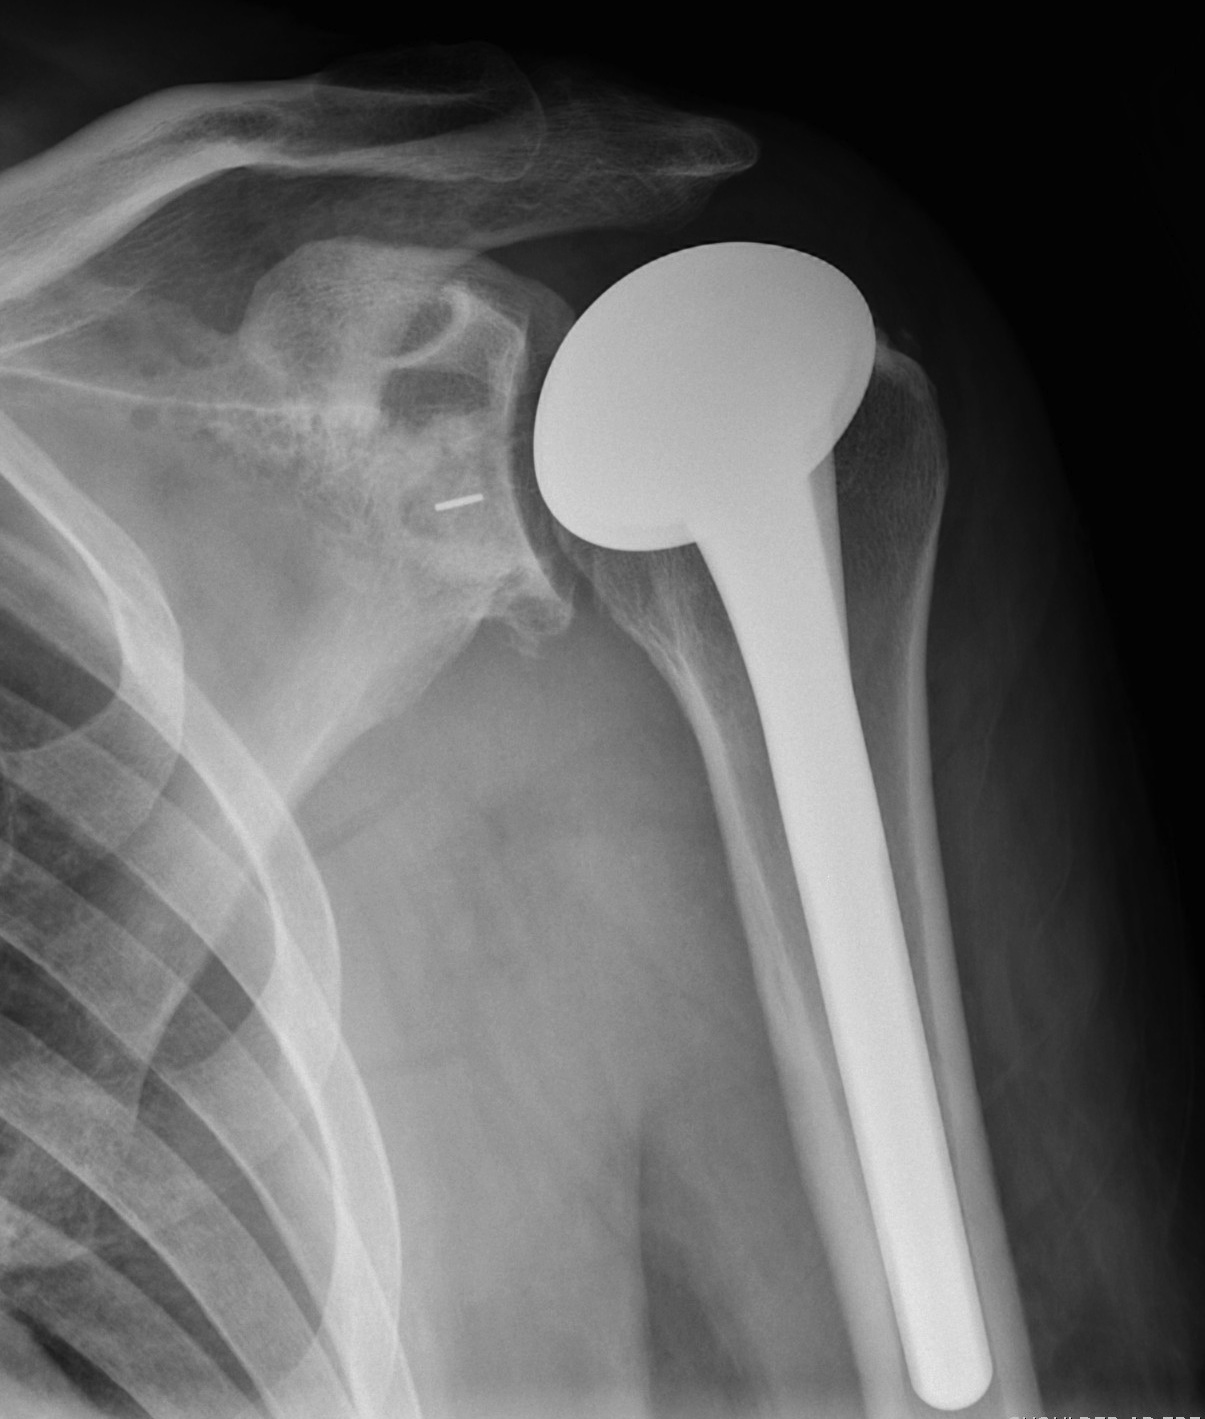

Arthroplasty

Indications

Acute unreconstructable fracture > 60